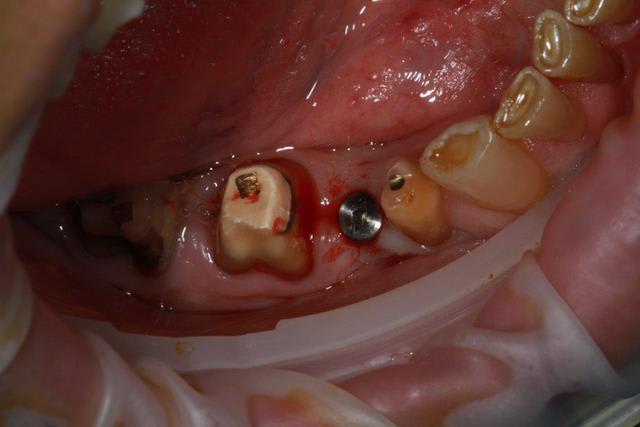

Nouveau patient, pose d'un implant il y a 2 mois....échec sans raisons particulières, douleurs et dépose.

Ce matin repose d'un nouvel implant et comme je ne veux pas prendre de risque, et que les dents adjacentes doivent être couronnées, je pose un bridge en emax press, mais scellé au ciment provisoire...

alors là pas du tout, le patient vient me voir pour des implants, donc je fais une étude du cas absence des molaires supérieures, couronnes mandibulaires très ancienne 45 racine cassée, 44 dévitalisée mais passablement déchaussée, donc avulsion de 45 et pose d'un implant avant de refaire les couronnes 46/47 et l'ensemble.

Échec implantaire, et oui ça arrive, même dans un cas paraissant simple.

Dépose gratuite bien sur et repose gratuite aussi, le bridge n'est pas facturé non plus, il le sera sous forme de 2 couronnes que cette fois ci l'implant fonctionne ce que j’espère, ou laissé en bridge si l'implant devait être retiré.

dans le cas présenté, le but est de redonner confiance au patient, et pas du tout le fric.